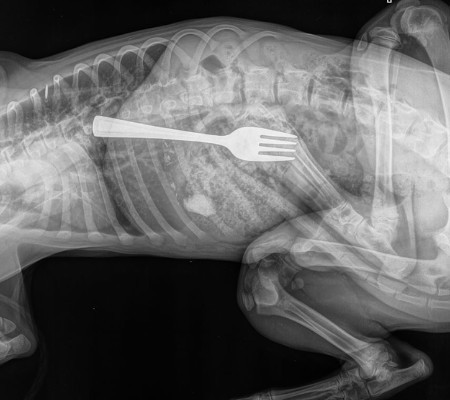

O pet foi levado às pressas para o Centro de Referência e Emergência Animal de Adelaide, onde foi realizado um raio-X que apontou a localização exata do item.

Ao noticiário, o veterinário responsável pelo caso, Matt Woodruff, afirmou que se não tivesse sido treinado para ocasiões como essas, teria achado que alguém photoshopou a imagem.  “Foi uma surpresa, foi a primeira vez que vi um cão comer um utensílio”, falou.